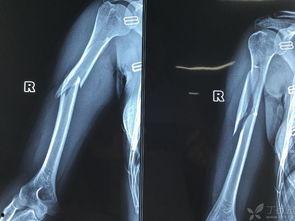

你那胳膊骨折了?别急,今天就来给你支个招,让你在家也能轻松恢复,还能跟着视频学学新技能!没错,就是那让人头疼的肱骨骨折恢复锻炼,今天咱们就来聊聊这个话题。

首先,你得知道,肱骨骨折可不是闹着玩的。这可是连接肩膀和肘部的重要骨骼,一旦骨折,恢复起来可就慢了。但是,只要方法得当,锻炼得法,恢复速度就能大大提高。不信?那就看看下面的视频吧!